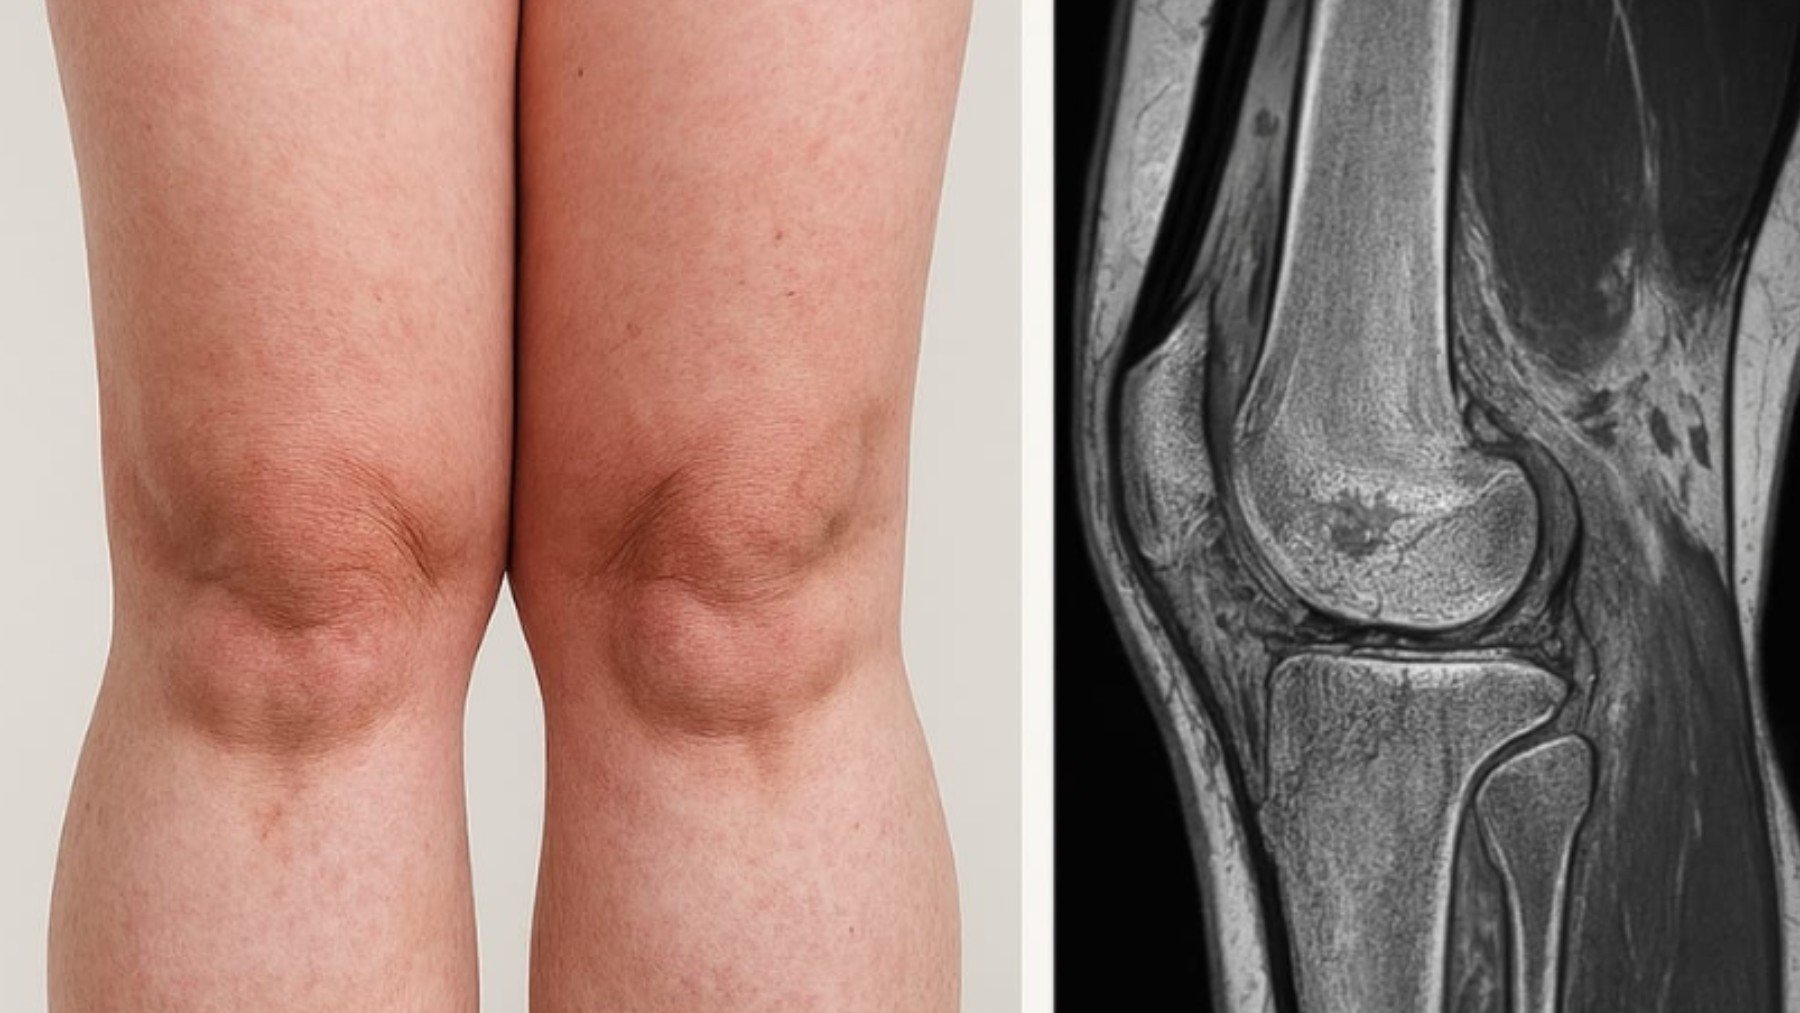

Pero, ¿qué es la lipedema? A diferencia del sobrepeso o la obesidad , el lipedema se caracteriza por una acumulación patológica de grasa en zonas específicas — piernas, caderas y brazos —, que no responde a dietas ni al ejercicio físico. Las pacientes suelen experimentar dolor espontáneo o al tacto, sensación de pesadez, tendencia a hematomas y una profunda carga emocional derivada de las alteraciones estéticas y funcionales.

Si no se trata a tiempo, el lipedema puede evolucionar hacia deformidades, sobrecarga articular y trastornos linfáticos que deterioran significativamente la calidad de vida.